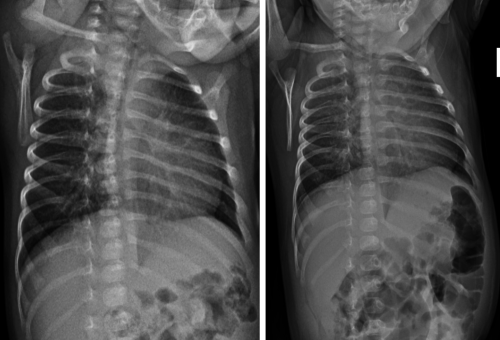

The patient's head CT and all laboratory studies resulted as normal. The initial skeletal survey did not show any radiographic evidence of injury. A follow-up skeletal survey was recommended by the child abuse team.

A FUSS was completed 2 weeks later.

Image 3. Oblique views of left ribs. AP chest radiograph. A. Normal. B. Follow up, demonstrates healing changes with callus formation from the left 2nd through 8th costovertebral junction

Image 4. Frontal view of left tibia and fibula. A. Normal. B. Follow up. Irregularity of proximal tibial metaphysis, concern for healing classic metaphyseal lesion